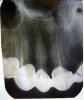

EJIeHa Опубликовано 25 февраля, 2011 Поделиться Опубликовано 25 февраля, 2011 Здравствуйте!!! 8 декабря 2010 года мне поставили металлокерамический мост из 8ми единиц. На второй день после приема горячей пищи, зуб начал реагировать, но затем сразу успокаивается. После того, как я побывав на улице, захожу в теплое помещение, то зуб начинает пульсировать. Это длится до тех пор, пока я не согреюсь. Я сразу же обратилась к лечащему врачу, но вразумительного ответа я не получила. Мост снять, они сказали не получится. Беспокоит верхняя 1 или 2ка справа (сама понять не могу). Выкладываю снимок:1й снимок (Сделан 8 декабря)2й снимок (Панорамный снимок 26 января)3й-4й снимки (2 февраля)Помогите пожалуйста, только на Вас надежда!!!Если можно, дайте свой комментарий по поводу всех пролеченных зубов.Большое СПАСИБО. Ссылка на комментарий

EJIeHa Опубликовано 26 февраля, 2011 Автор Поделиться Опубликовано 26 февраля, 2011 (изменено) Посмотрите пожалуйста,на верхнюю тройку и нижние 5-ка и 7 - ка, в каком они состоянии?Спасибо.1й снимок 30 ноября 2010 http://pixs.ru/showimage/1yjpg_6326196_1765899.jpg2й снимок 10 декабря 2010 http://pixs.ru/showimage/2yjpg_3128753_1765903.jpg Изменено 26 февраля, 2011 пользователем EJIeHa Ссылка на комментарий